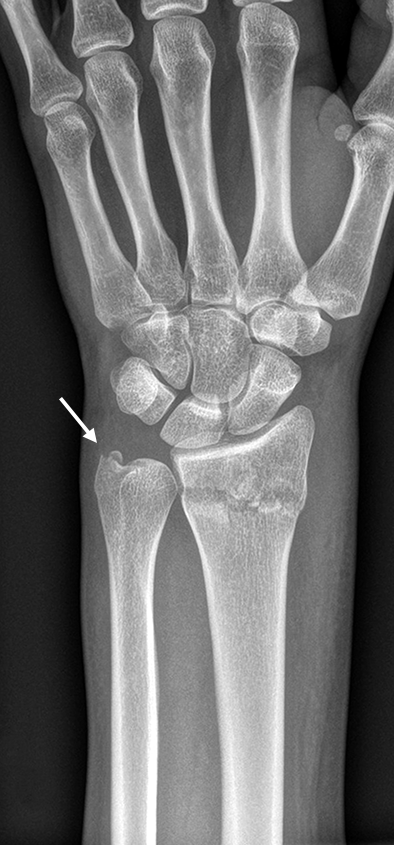

The patient was a 25-year-old woman who sustained a displaced, unstable extraarticular fracture of the left distal radius while snowboarding.

After closed reduction a dorsal re-dislocation of 25° occurred (Fig 3a). There are additional apparent signs of instability: dorsal comminution (Fig 3a) and fracture of the ulnar styloid (Fig 3b). Therefore, a considerable potential for further dislocation is present which is likely to occur in a cast. This young, active, and demanding patient wishes to return to her activities as early as possible. This can only be achieved with an operative fracture fixation. The nail was chosen instead of a plate. This allowed an almost instant functional use of her hand, which allowed her to return to work at 2 weeks postoperatively without additional fixation or a splint and full unprotected function of her wrist at 6 weeks.